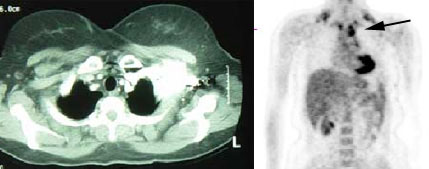

Scott WilliamsPETPET > PET tumor imaging > MelanomaApril 2, 2002Infections-InflammatoryInfect > Parasites > PCP > Images > PCP-retic-nodularApril 2, 2002Inhalation-LungsInhale > SilofillersApril 2, 2002Infections-InflammatoryInfect > FungusApril 2, 2002TumorTumor > Malignant > AdenoidcysticApril 2, 2002Infection-InflamationInfection-Inflammation > In-111 WBC > Images > Spine osteoApril 2, 2002PETPET > PET tumor imaging > Breast CancerApril 2, 2002CardiacCardiac > Valve > MR > ImagesApril 2, 2002Pulmonary ImagingGeneral > Anatomy > Images > IAPB-malpositionedApril 2, 2002Miscellaneous PulmonaryMisc > TransplantApril 2, 2002Previous PagePage 110 of 265Next PageTop StoriesCT5-year CTC screening interval is appropriate for colorectal cancerThe study's findings add to an ongoing conversation about the use of CTC for colorectal cancer screening.MRIASTRO: Daily MRgRT recontouring improves prostate treatment outcomesRadiation Oncology/TherapyASTRO: Radiation therapy comparable to surgery for early-stage lung cancerCTCT use in the ED has more than doubled over a decadeSponsor ContentDigital Innovations Shaping the Future of Radiology